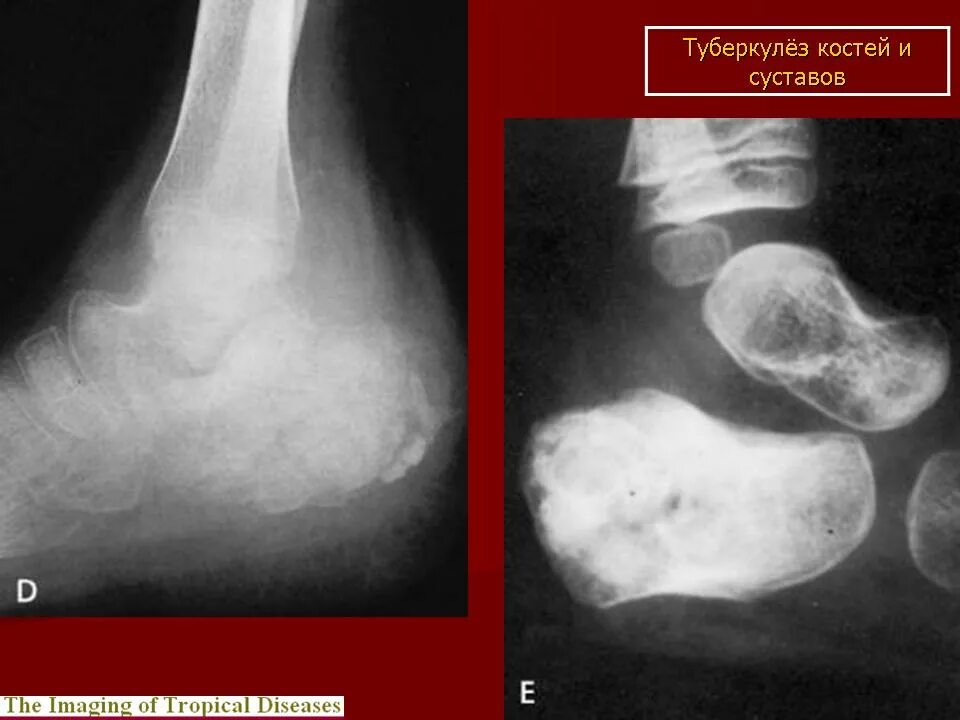

Туберкулез суставов симптомы